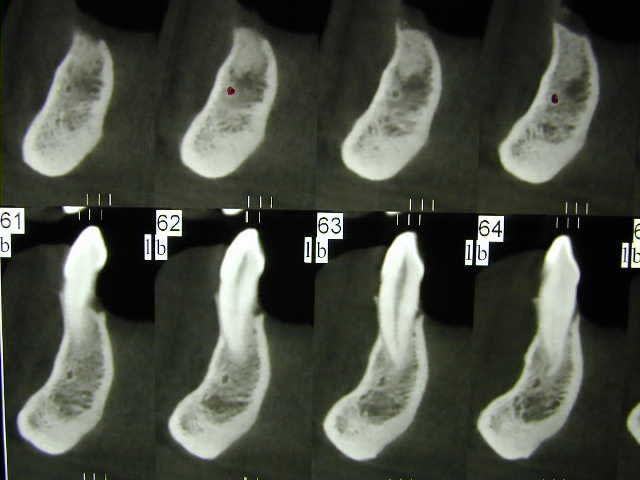

2)Sur le scanner j'ai l'image du nerf dentaire et d'un nerf en dessous, de quoi s'agit-il ?

> 2)Sur le scanner j'ai l'image du nerf dentaire et d'un nerf en dessous, de quoi s'agit-il ?

l'artère alvéolaire non ? en zone de spix elle est dessus puis dans son trajet mandibulaire en dessous du NAI